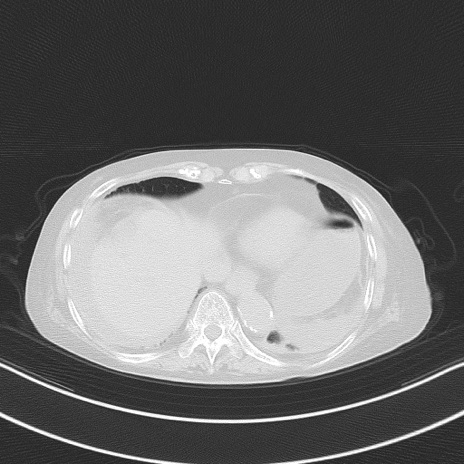

横断像

他院CT